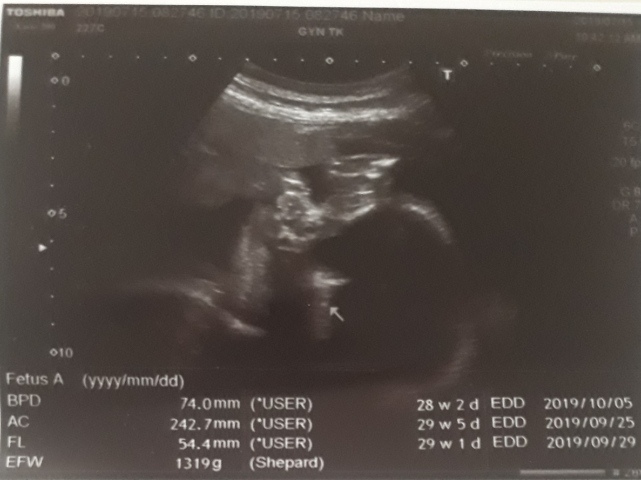

| 仙人掌(2019/07/15)的真心話 星期一 天氣晴 編號19-185 |

29週又3天↓

近七次產檢資料統計(BPD量出來竟然比兩星期前還小,可能有錯誤)↓

| 日期/項目 | BPD | AC | FL | EFW | 心跳 |

| 2019年03月04日 | 無資料 | 無資料 | 無資料 | 無資料 | 無資料 |

| 2019年04月01日 | 28.9mm | 77.9mm | 14.2mm | 107g | 153 |

| 2019年04月29日 | 41.7mm (44%) | 125.7mm (61%) | 28.9mm (103%) | 241g (125%) | 150 |

| 2019年05月22日 | 53.4mm (28%) | 160.6mm (28%) | 34.6mm (20%) | 408g (69%) | 150 |

| 2019年06月03日 | 58.3mm (9%) | 179.6mm (12%) | 38.2mm (10%) | 584g (43%) | 157 |

| 2019年07月01日 | 74.9mm (28%) | 208.8mm (16%) | 50.1mm (31%) | 1099g (88%) | 141 |

| 2019年07月15日 | 74.0mm (-1%) | 242.7mm (16%) | 54.4mm (8%) | 1319g (20%) | 133 |

| BPD:胎兒頭骨橫徑 AC:胎兒腹圍的長度 FL:胎兒大腿骨的長度 EFW:胎兒的體重 括弧內百分比為較上次產檢的成長比例 | |||||